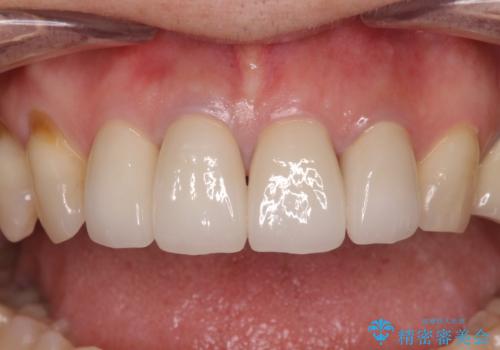

左右対称で明るく自然な前歯に仕上げることができました。